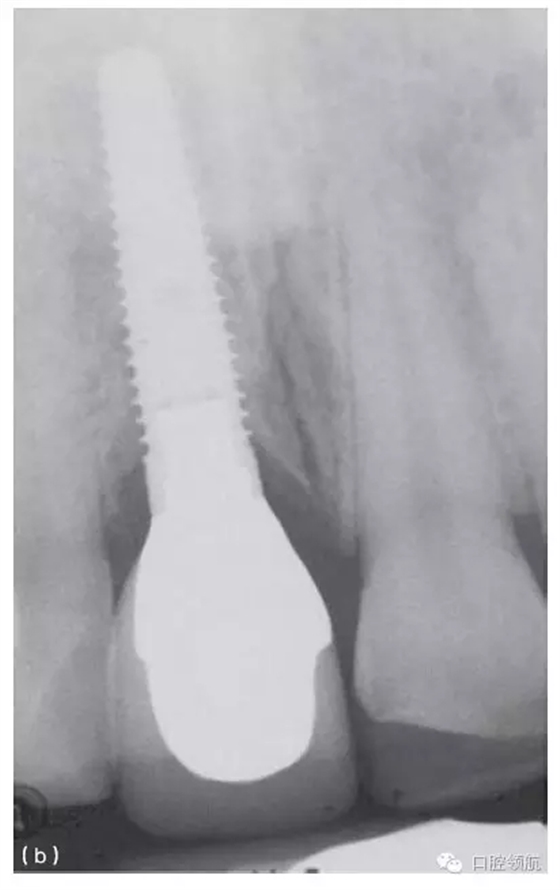

當(dāng)鄰間隙的骨高度良好,隨著時(shí)間的推移,軟組織可充填小的間隙(圖10.35a,b)。很顯然,軟組織頂部到骨之間的距離,對(duì)于維持天然牙和種植體之間的牙齦乳頭是很重要的。一項(xiàng)研究報(bào)道,在26名患者的上頜前牙區(qū),植入27顆單個(gè)種植體,對(duì)52個(gè)牙齦乳頭進(jìn)行評(píng)估,來(lái)研究鄰間區(qū)牙槽嵴高度對(duì)種植體和天然牙之間牙齦乳頭的維持作用。研究發(fā)現(xiàn),種植體冠與天然牙鄰面觸點(diǎn),到鄰面牙槽嵴頂?shù)木嚯x≤5mm時(shí),牙齦乳頭100%存在。而當(dāng)這個(gè)距離≥6mm時(shí),僅有50%的牙齦乳頭存在。

圖10.35 (a)上頜中切牙周圍的牙齦乳頭充填,形成了良好的軟組織外觀。(b)(a)圖中種植體冠的X線片顯示,相對(duì)修復(fù)體和種植體來(lái)說(shuō),鄰面牙槽骨處于理想的位置。(c)下頜種植支持式的局部固定義齒,采用牙齦色的烤瓷來(lái)改善頸部外觀。(d)復(fù)制的上頜全口義齒的前面觀,一側(cè)的頰側(cè)翼板被去除,以模擬上頜全口固定義齒的外觀。(e)右側(cè)觀唇部的支撐效果。(f)左側(cè)觀唇部的支撐效果。這一側(cè)對(duì)唇部的支撐明顯不如對(duì)側(cè)。